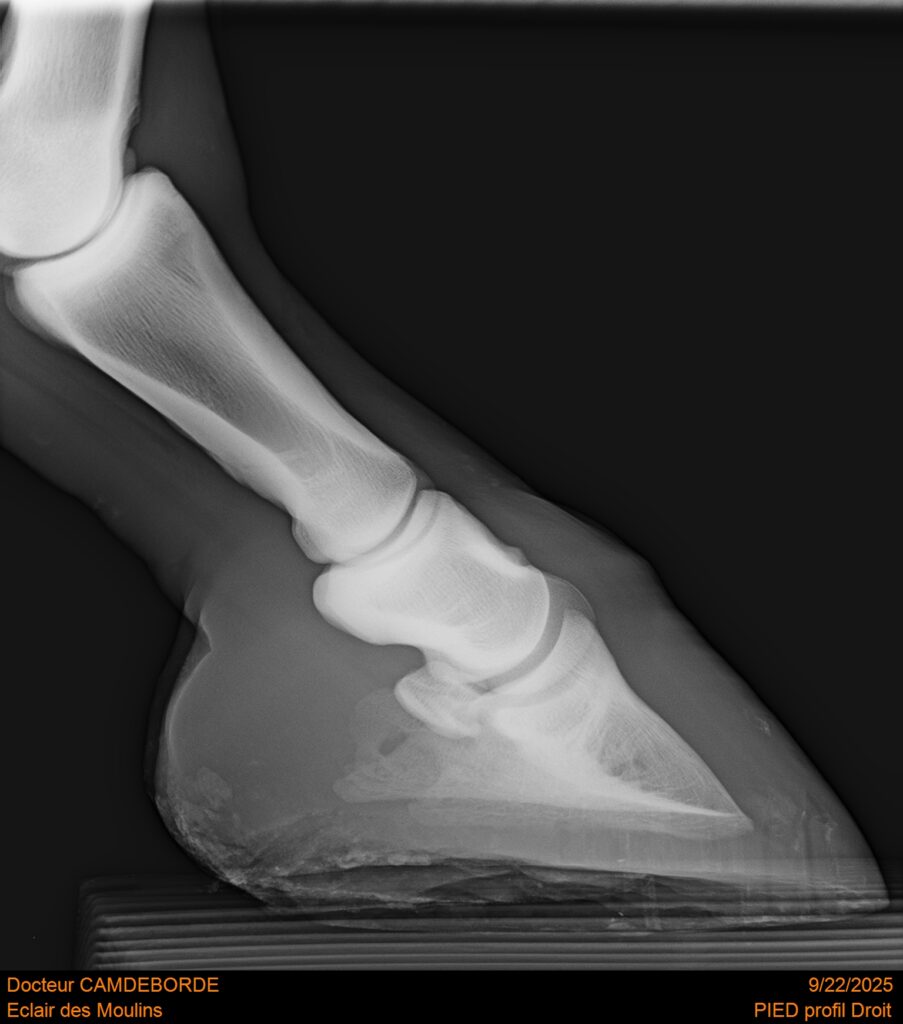

RADIOS ET CLINIQUE